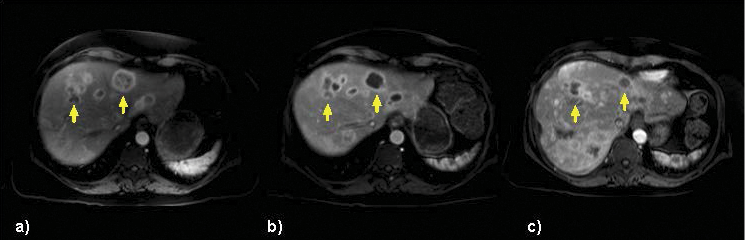

New research on the minimally invasive, image-guided therapy Yttrium-90 (Y-90) radioembolization shows promise in treating breast cancer that has spread to the liver when no other treatment options remain.

In research presented at the 2014 Society of Interventional Radiology Annual Meeting, Dr. Lewandowski and colleagues treated 75 women (ages 26-82) with breast cancer liver metastases, all of whom had progressive disease. In addition, 85 percent of these women had multiple liver tumors and 77 percent had disease outside the liver.

Researchers determined that the tumors got smaller or remained stable in 98.5 percent of the patients after radioembolization, while tumor reduction of more than 30 percent occurred in 24 patients. Additionally, these women experienced no major side effects.

With systemic treatments like chemotherapy, “you inject something into a vein and hope it gets into the right area. Sometimes it does, but if not, whole-body side effects like hair loss or diarrhea can occur,” said study author Riad Salem, M.D., a professor of radiology, medicine-hematology/oncology and surgery-organ transplantation at Northwestern. “With radioembolization, we are delivering a very potent dose of radiation only to the liver, thereby achieving better anti-tumoral treatment with fewer side effects.”